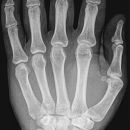

Hand a.p. (dorsovolar)

Lagerung

Patient sitzt seitlich am Tisch, der abgewinkelte Unterarm und die Handflächen liegen auf, Finger leicht gespreizt, evtl. Sandsack zur Fixierung auf den Unterarm legen.

Zentralstrahl

Auf Objekt- und Kassettenmitte.

Anmerkung

Übersichtsdarstellung des Skeletts bei Frakturen, Arthrosis und Deformierung der Gelenke, sowie chronischer Polyarthritis (Rheuma).

Qualitätskriterien

Vollständige Abbildung der ganzen Hand einschließlich aller Fingerendglieder und des Handgelenkes.